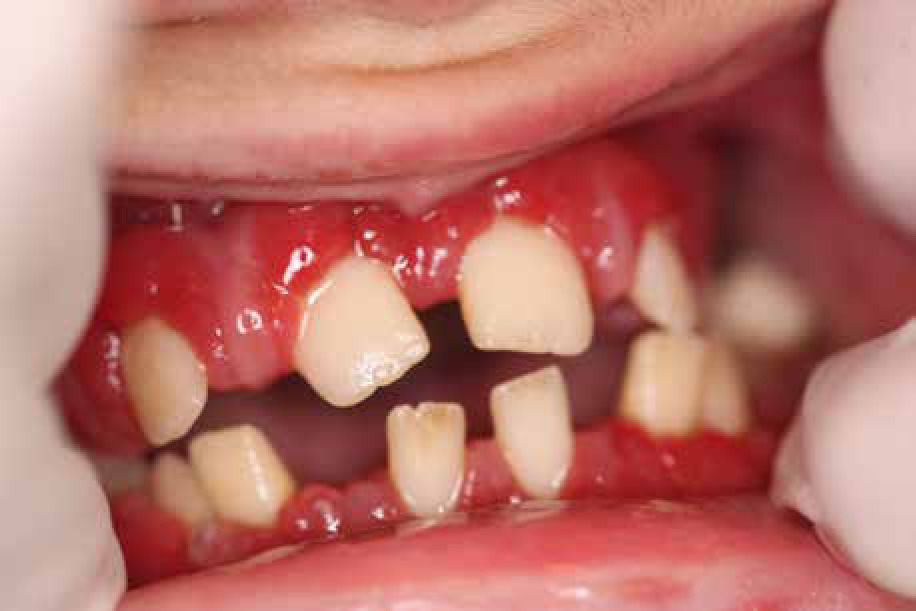

When he was 5 years of age the intraoral examination revealed incomplete primary dentition with five missing teeth, marginal gingivitis, interdental papilla hypertrophy, carious lesions in seven primary teeth, and one permanent tooth of various degrees of advancement for conservative treatment (Fig. 1). The patient was qualified for simultaneous dental treatment under general anesthesia. A panoramic radiograph picture was taken showing the advanced destruction of the alveolar bone in the maxilla and the alveolar part of the mandible. Three primary teeth were completely devoid of bone base. The roots of the lower incisors were only half of their normal length (Fig. 2). Under antibiotic protection (amoxicillin with clavulanic acid at a dose of 30 mg/kg), professional removal of dental plaque and conservative treatment of teeth extraction of four primary teeth with complicated caries and periodontitis were performed. The patient was provided with permanent dental care.